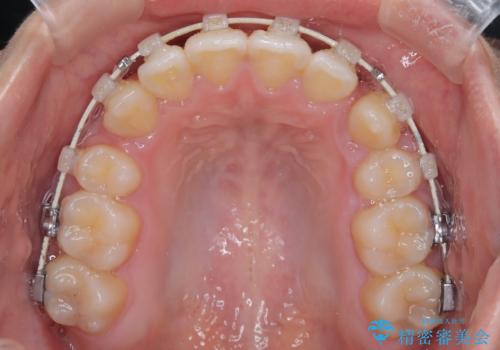

- 矯正装置

- 審美装置

- 八重歯を主訴に来院されました。

左側犬歯が埋伏していましたが、第一小臼歯(4番目の歯)を抜歯したことでできたスペースに牽引し、右側の飛び出した八重歯を含め、歯全体を整列することができ患者様も満足していただきました。

犬歯牽引を行うかはCTを撮影し判断を行なっています。